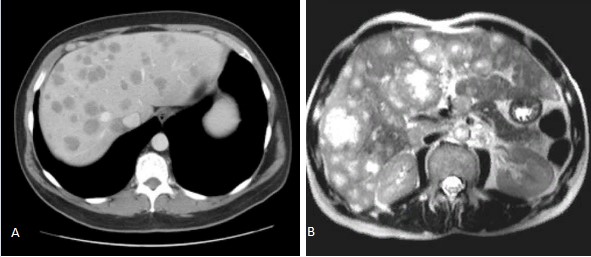

Методы динамического контрастирования печени на МРТ

Раздел: Снимки-подсказки